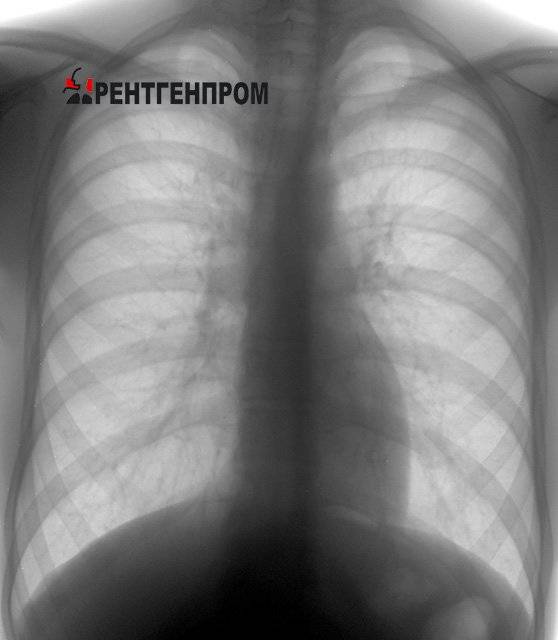

Снимок здоровых лёгких

При оценке результатов цифровой флюорографии врачи рассматривают следующие позиции при помощи рентгеновского облучения:

- мягкие ткани;

- целостность костных элементов;

- расположение трахеи;

- наличие кальцинатов;

- контуры сердца;

- лёгочные поля.

Исследование проводится в передне-задней проекции. Снимки информативны и дают возможность оценить или выявить наличие патологии в лёгких.